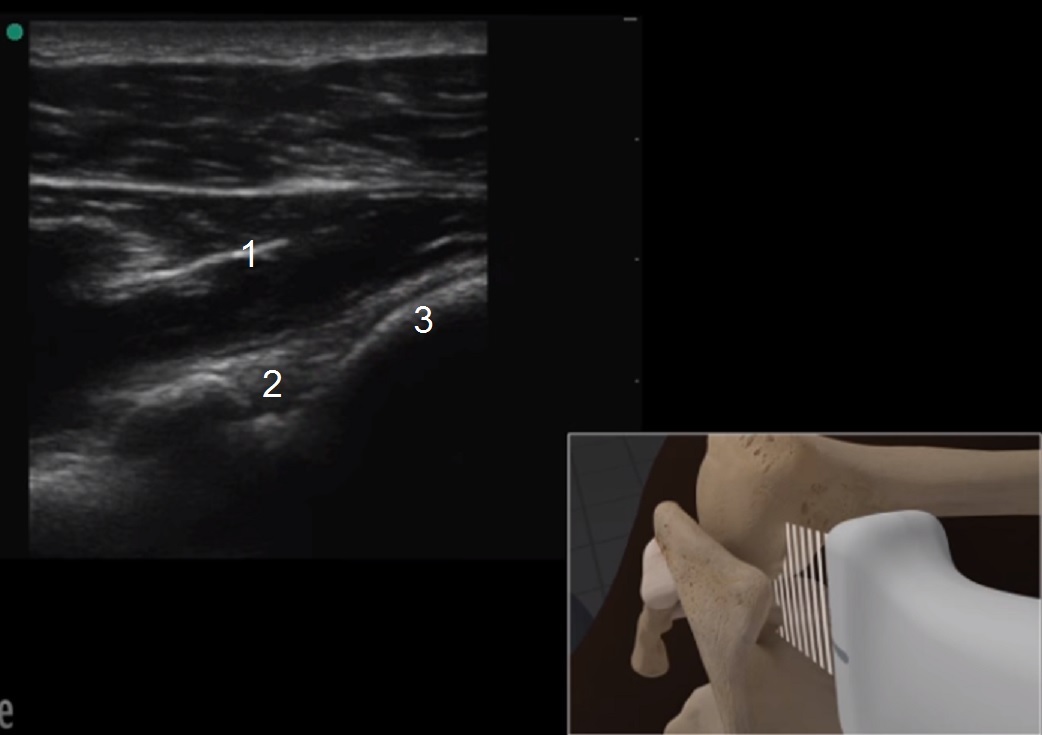

肩甲上腕の解剖学 1 画像

棘下筋

肩関節窩唇

上腕骨頭